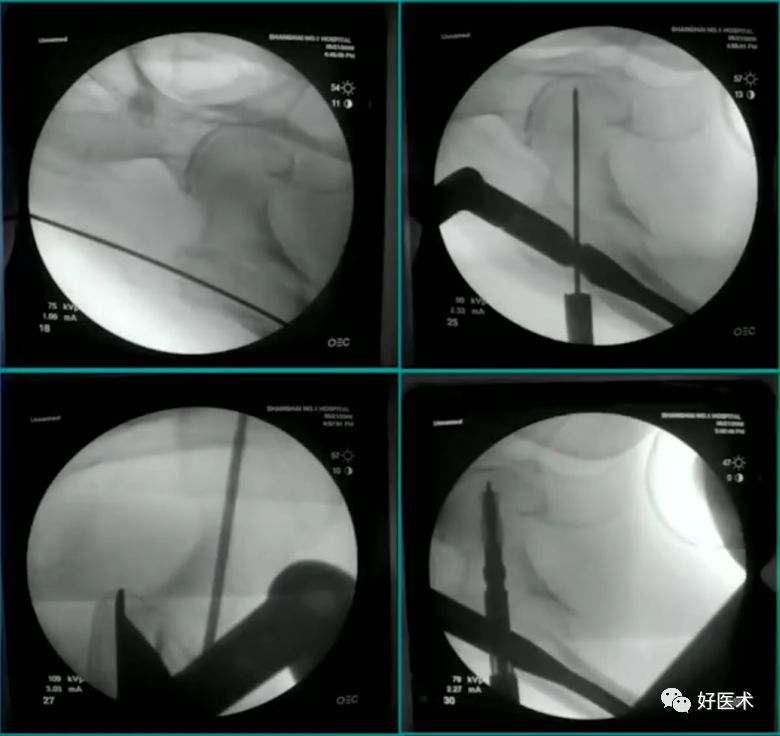

病例:男,34岁,高处坠落伤,仅骨折余正常

处理方法:

-

髓内钉(开放VS闭合)

钢板

其他

术前牵引

开口、定位

术中过程